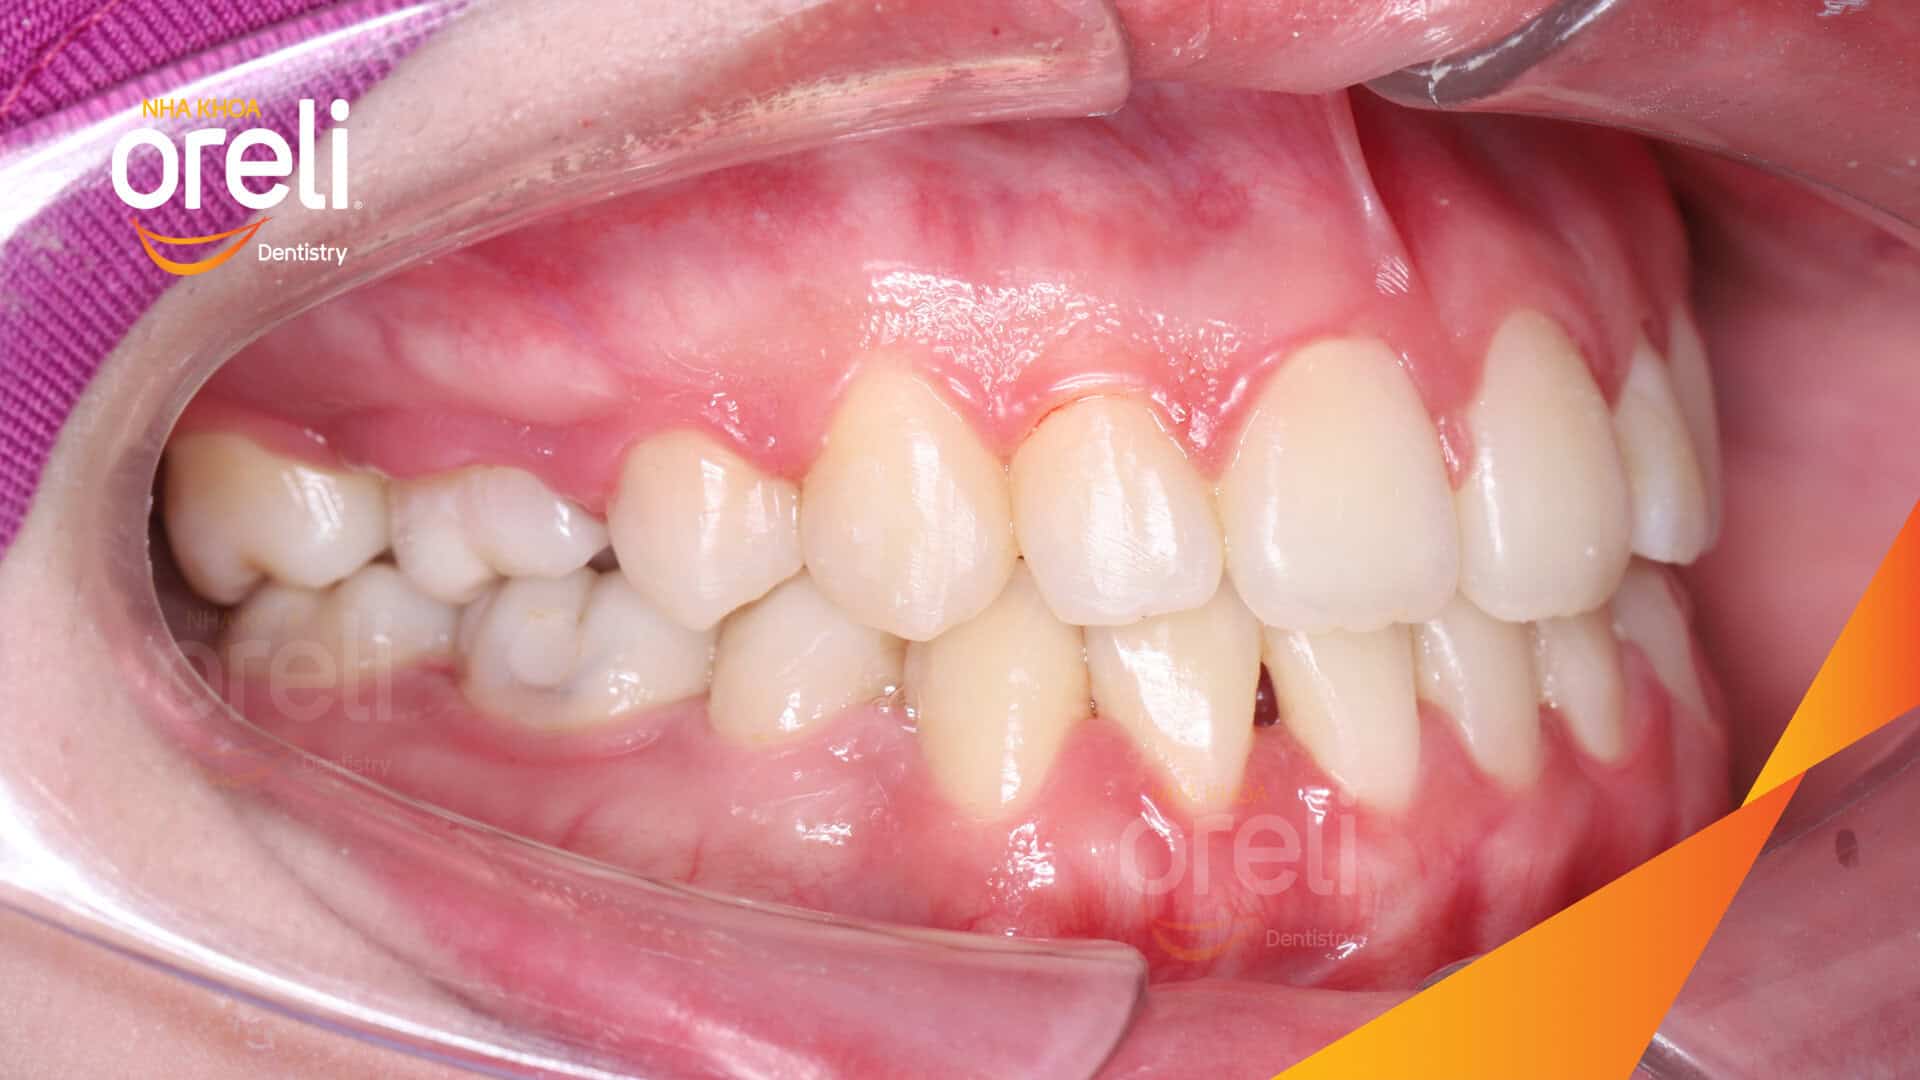

Hành trình thay đổi nụ cười ca lệch khớp cắn hạng 3, hàm dưới trượt ra trước và nhô xương hai hàm.

Tình trạng này không chỉ ảnh hưởng đến thẩm mỹ khuôn mặt mà còn gây khó khăn trong ăn nhai và phát âm. Thông qua quá trình niềng răng được cá nhân hóa, khách hàng đã từng bước cải thiện khớp cắn và lấy lại sự tự tin trong giao tiếp.

Hình ảnh thực tế